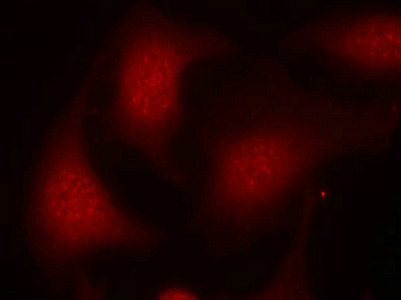

Immunofluorescence staining of methanol-fixed Hela cells using Rb(Phospho-Ser795) Antibody.